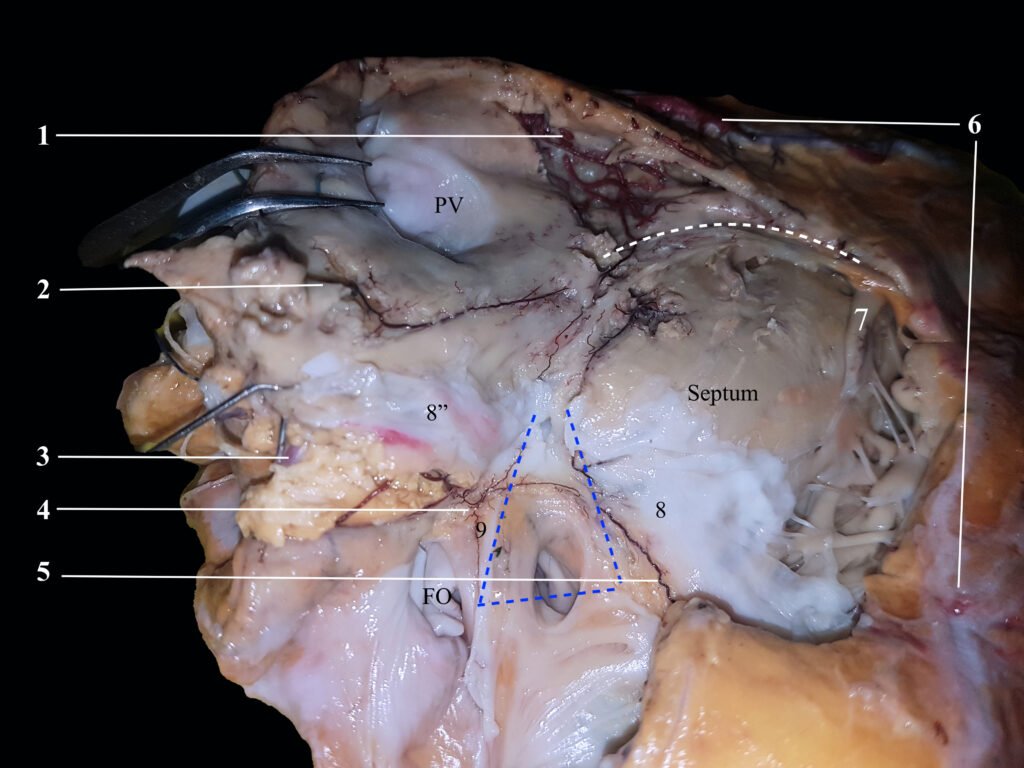

En las siguientes fotografías se ilustran las cuatro fuentes vasculares del nodo atrioventricular.

Dos son conocidas hace décadas, las últimas dos demostradas por nuestro laboratorio hace un par de décadas. Son -estas últimas- la arteria anastomótica auricularis magna o arteria de kugel y la arteria septal derecha.

Ambos vasos se ilustra cómo llegan al sistema de conducción.

El triángulo de Koch, señalado en punteado azul se ilustra con sus límites. la banda moderadora en punteado blanco.

La arteria primera septal (1), rama de la descendente anterior (6), se anastomosa con la arteria septal superior derecha (2) rama del origen de la coronaria derecha. Obsérvese cómo se trata de un ramo septal.

La arteria coronaria derecha (3) apenas visible en la preparación y la arteria de Kugel (4) anastomosándose con la clásica “arteria del nodo a-v o rami septi fibrosi” (5).

Lo invitamos a aumentar la fotografía para lograr el detalle de lo ilustrado.